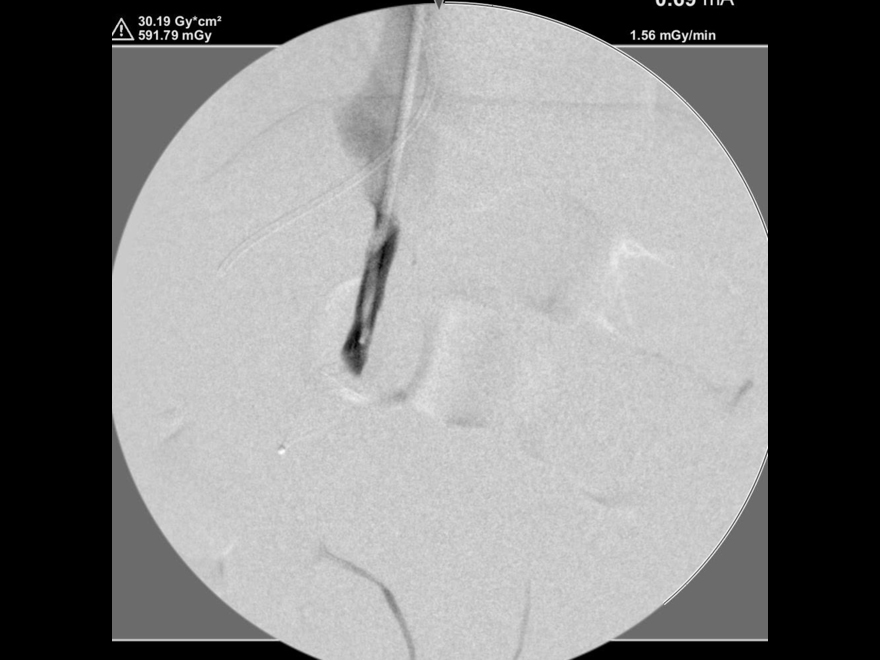

カテーテルでのシャント血管の造影検査

プラグ塞栓後の造影検査